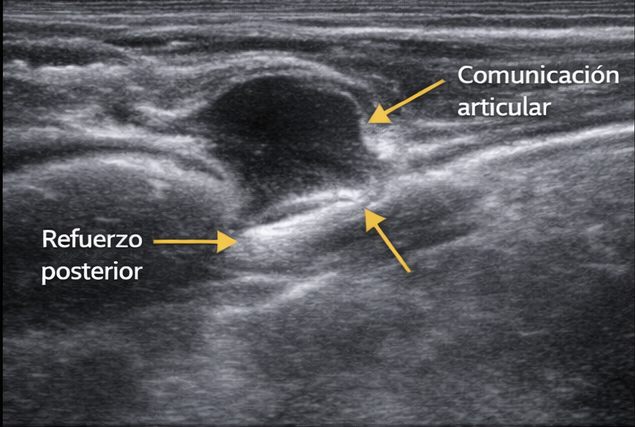

PRUEBA DE ELECCIÓN. La ecografía con transductores lineales de alta frecuencia (7-15 MHz) es diagnóstica en la mayoría de los casos.

- 🔹 Hallazgo característico: Masa anecoica (negro), bien delimitada, de paredes finas, con refuerzo acústico posterior. Puede ser lobulada o tener tabiques internos.

- 🔹 Localización: Se identifica la relación con la articulación o la vaina tendinosa de origen, así como el pedículo de comunicación.

- 🔹 Doppler color: Sin flujo vascular (diferencia de tumores sólidos).

- 🔹 Compresibilidad: El quiste suele ser compresible con la sonda, a diferencia de los tumores sólidos.